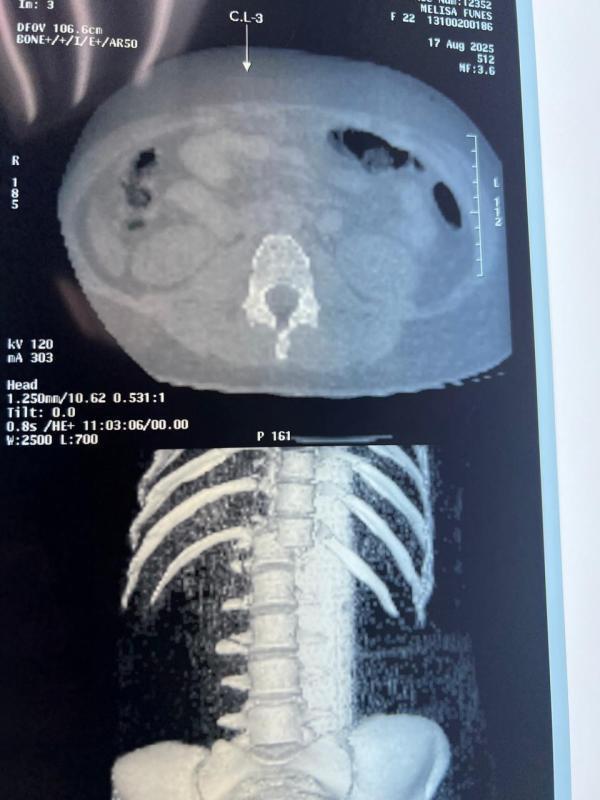

La joven madre, de 22 años, sufrió varias fracturas, la lesión más grave la presenta en la columna y necesita medio millón de lempiras para recuperarse.

Esta es la lesión de la columna que presenta Melissa y por lo cual se mantiene postrada en el hospital Mario Catarino Rivas. "El dueño de los juegos dijo que ellos están cubriendo los gastos. Es cierto que llegó, pero no dejó ni un cinco", dijo una pariente de Melissa.